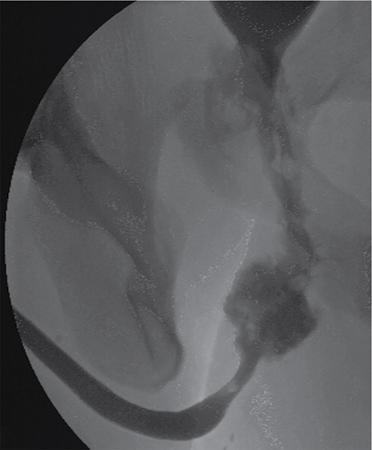

Aniruddha Joshi URETHRAL DIVERTICULUM (URETHROCELES) Urethroceles are focal outpoching of urethra. Ultrasonography (US) and MRI have improved our diagnostic ability and understanding of the disease. Women especially those with stress incontinence are affected more frequently than men. Most of the women are between the ages of 30 and 50 years. These patients commonly present with nonspecific clinical symptoms – dysuria, postvoid dribbling, dyspareunia, frequency/urgency, recurrent haematuria, stress incontinence. Some of the patients may develop stones within the diverticulum. Repeated infection and irritation predispose to malignant transformation of the lining urothelium. Urethral diverticulum is an epithelized outpouchings of the urethral lumen into the surrounding periurethral connective tissue. Aetiology of the urethral diverticulum is unknown. Current hypothesis states that repeated infection and obstruction of the periurethral and paraurethral glands (Skene’s gland) results in formation of cyst/abscess. At some point these rupture into the urethral lumen and connect to urethra via a neck or ostia. These outpouchings may be simple in nature, may partially encircle the urethra (saddlebag), or may completely envelop the urethra. Sometimes, they extend proximally beneath the bladder neck and trigonal area. Complicated anatomical patterns, however, may exist with multiple ostia. Iatrogenic damage to the urethra may also play a role in formation of the diverticulum. Voiding cystourethrography and double-balloon catheter urethrography (DBU) were used to be considered investigations of choice (Fig. 10.15.1.1). Transabdominal, transvaginal, transperineal or transluminal USG techniques have been described with the patient in the dorsal lithotomy or supine position. These techniques are operator-dependent leading to drawback in diagnosing of urethral. USG provided particular benefit in differentiating a septated urethral diverticulum from multiple urethral diverticula compared with MRI. Poor soft tissue contrast causes limitation to the conventional contrast-enhanced CT. Urethral diverticulum may be visualized at as a hypodense mass with wall thickening and enhancement at the level of the pubic symphysis. However, urethral calculi in the dependent portion of diverticula can be reliably shown. Recently MRI has become the imaging study of and is strongly advocated before performing any surgery. Diverticuli appear T1 hypointense and T2 hyperintense. IV gadolinium can be administered for detection of inflammation, infection or malignancy (Fig. 10.15.1.2). The differential diagnosis of urethral diverticulum includes: vaginal wall cysts, leiomyoma, Skene’s gland abnormalities, Gartner’s duct abnormalities, urethral prolapse, ectopic ureterocele urethral diverticular adenocarcinoma and urethral caruncle. URETHRAL TRAUMA Urethral traumatic injuries may be of blunt, penetrating or iatrogenic types. Other uncommon causes of injuries are penile fracture and injuries resulting from pancreas transplantation. Diagnosis and extent of the urethral injuries require high-quality imaging for effective treatment planning. Male urethral injuries are much more common than female urethra. In clinical setting of trauma, blood at the external urethral meatus, vaginal introitus and haematuria may be seen, but these are unreliable signs. Complete urethral disruption, there may be overdistended bladder with inability to void, perineal ecchymosis and on DRE impalpable/high riding prostate. Dysuria, urinary urgency and suprapubic discomfort can ensue in the chronic stages of incomplete urethral injury due to complicating strictures. Urethral trauma is associated with blunt trauma, penetrating or iatrogenic types. Most commonly associated with motor vehicle accidents. Other less common causes are penile fracture, urinary extravasation in pancreas transplantation, instrumental childbirth. Urethral traumatic injuries occur commonly associated with motor vehicle accidents. Depending on location, these can be anterior or posterior urethral injury. Anterior urethral injuries are associated with direct blow to perineum, straddle injury, penetrating traumas, penile fracture and iatrogenic. Bulbous urethra is most commonly injured in this. Posterior urethral injury is far more common. These are associated with road traffic accident and fall from a height. Posterior urethra is in close relation to the pubic bones and the puboprostatic ligaments. Urethra is also susceptible to injury by the displaced fracture fragments. The distal membranous urethra is especially at risk. Female urethral injury is rare due to short length, internal location and less rigid attachment of the urethra to the adjacent pubic bone. And in severe pelvic trauma during road traffic accidents, there can be bladder neck injuries extending into the urethra. Iatrogenic traumas may result in injury at any level of the urethra and are seen as a consequence of urological interventions, surgery or radiotherapy. In acute traumatic setting, any visceral/vascular injury should be managed to achieve haemodynamic stability. Patients with clinical signs indicative of urethral injury should be considered for immediate urethrography. On imaging if urethra appears intact, catheter may be inserted. If there is urethral or bladder injury, a suprapubic catheter should be inserted and later to be posted for surgery. Patients without clinical signs of urethral injury do not require immediate urethral imaging. If inadvertently blind catherization is done, it may complicate haemorrhage or increase the degree of urethral tear. On plain radiography, presence of pelvic fractures with disalignment should raise suspicion for urethral injury. Fractures of ischiopubic rami or separation of the symphysis pubis is more indicative of urethral injury. It is the standard diagnostic investigation for evaluation of a male urethral injury. Ideally ascending (or retrograde) and descending (or antegrade) urethrohraphic studies should be performed for evaluation of anterior and posterior urethra. And on follow-up imaging retrograde imaging is required. In traumatic setting, patient mobility and proper imaging techniques are not always possible. In these cases, foam cushions may be placed underneath the patient to help maintain that position, the tube may be rotated to a 30-degree left anterior oblique angulation or the table may be elevated to a 45-degree angle during voiding with a footrest. Urethrogram allows identification of the site of injury and extent of any injury. Any extravasation outside the urethra is pathognomonic for urethral injury. Prostatomembranous urethra is commonly injured just above the urogenital diaphragm. On excretory urography, high-riding urinary bladder is seen due to disruption of puboprostatic ligaments and haematoma in the pelvis. Extravasation of contrast extravasation can be seen adjacent to the posterior urethra and sometimes into the pelvic extraperitoneal space (Fig. 10.15.2.1).